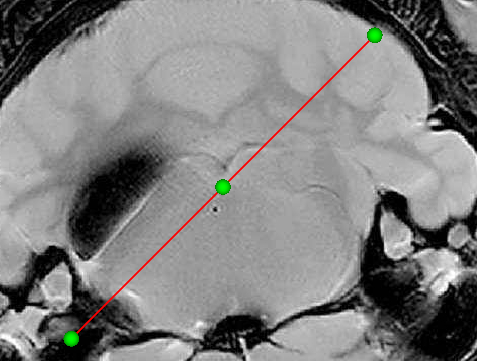

想做一个定位线,通过输入三个位置的坐标创建3个Handle+1条直线的控件的设计,如图所示:

1.两端的结点控制以中间的结点为中心可以旋转。

2.抓住中间的结点或者线条,可以实现整个控件widget的移动

3.中间结点Handle只能沿着线条可以移动位置